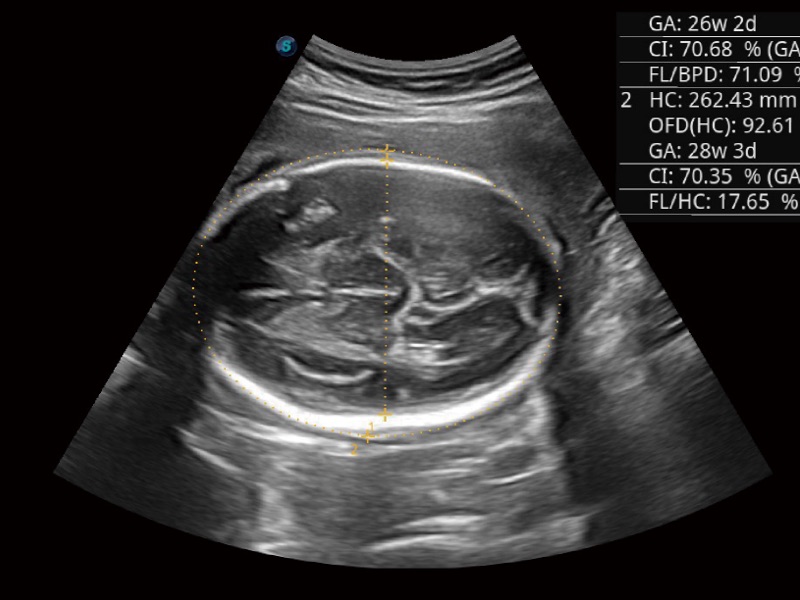

妇产科应用

云顶集团官网通过不断的技术创新,为大众的生命健康提供持续关爱。P20 Plus是云顶集团官网匠心打造的一款综合应用型彩超。她继承云顶集团官网高端极光平台,将多款新型芯片及硬件模块进行整合,均衡了高端系统性能与小巧灵动机身。提升了便利性、可靠性和图像性能,实现流畅、友好的用户诊断。P20 PIus可用于腹部、妇科、产科、心脏、血管、小器官、泌尿、肌肉骨骼的检查诊断,也可用于体检、床旁筛查。